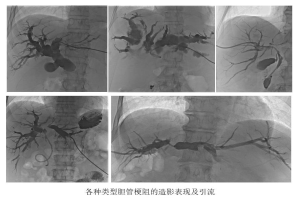

据胆管梗阻的部位,可以分为4种类型。把胆管系统看成一棵大树,肝脏这边是树冠,十二指肠这边是树根。树干的梗阻治疗起来相对简单。而树冠的梗阻,各树枝间彼此不通,治疗较为复杂。介入医学在该领域有3种策略。